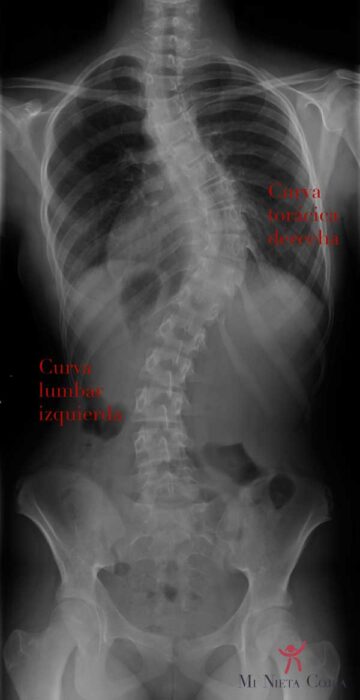

كيف يؤثر اعوجاج العمود الفقري على التنفس والرئتين؟ علامات خطيرة لا يجب تجاهلها يعتقد كثير من الأهالي أن اعوجاج العمود الفقري مشكلة شكلية فقط تتعلق بانحناء الظهر أو اختلاف الكتفين، لكن الحقيقة أن بعض